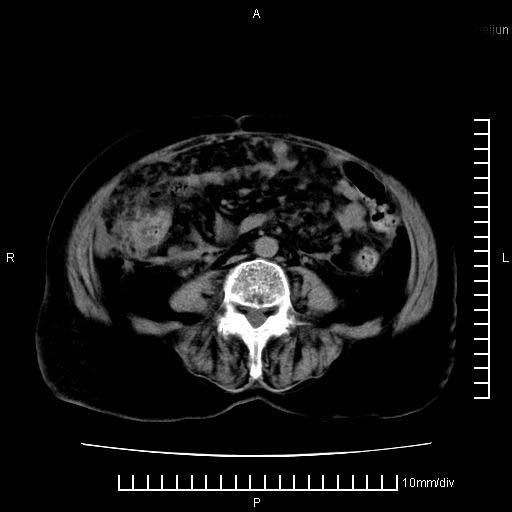

标题: CT28280:腹部增强:女性,80岁

上腹疼痛月余,外院核磁诊断胰腺癌。现临床示右下腹可明显触及包块,可片子上怎么没有看到?

胰腺体部癌累及周围器官,腹膜、粘连,临床摸到的可能是粘的组织

胰腺结构模糊,胰尾部见囊性包块,周围脂肪密度增高,左肾前筋膜增厚,胸水、腹水。不符合胰腺ca伴腹膜腔转移。考虑胰腺炎伴假性囊肿形成、胸腹腔积液。

1)考虑胰腺癌并胰腺假性囊肿形成。2)肝内低密度灶,不排除转移。3)右肾盂积水。4)腹水。5)右侧胸腔积液并右肺下叶部分膨胀不全。